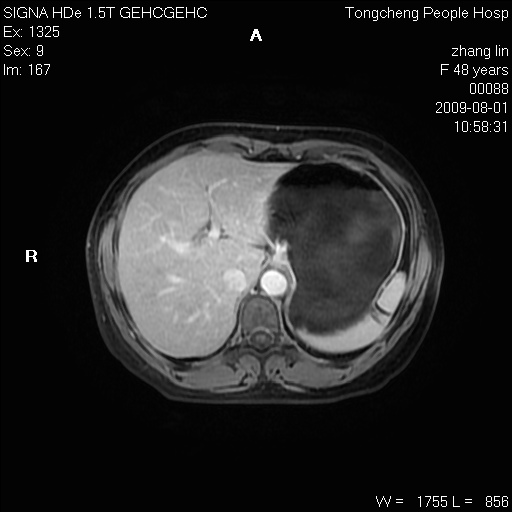

女,48岁。健康体检,彩超发现右肾占位性病变。平素健康。

临床诊断:右肾占位性病变,性质待定(囊肿?肿瘤?)。

上中腹部mr平扫+增强扫描,图像如下:

右肾上极见一类圆形病灶,t1wi呈等信号t2wi呈等高混杂信号,三期增强无强化,边界清---考虑囊肿出血。